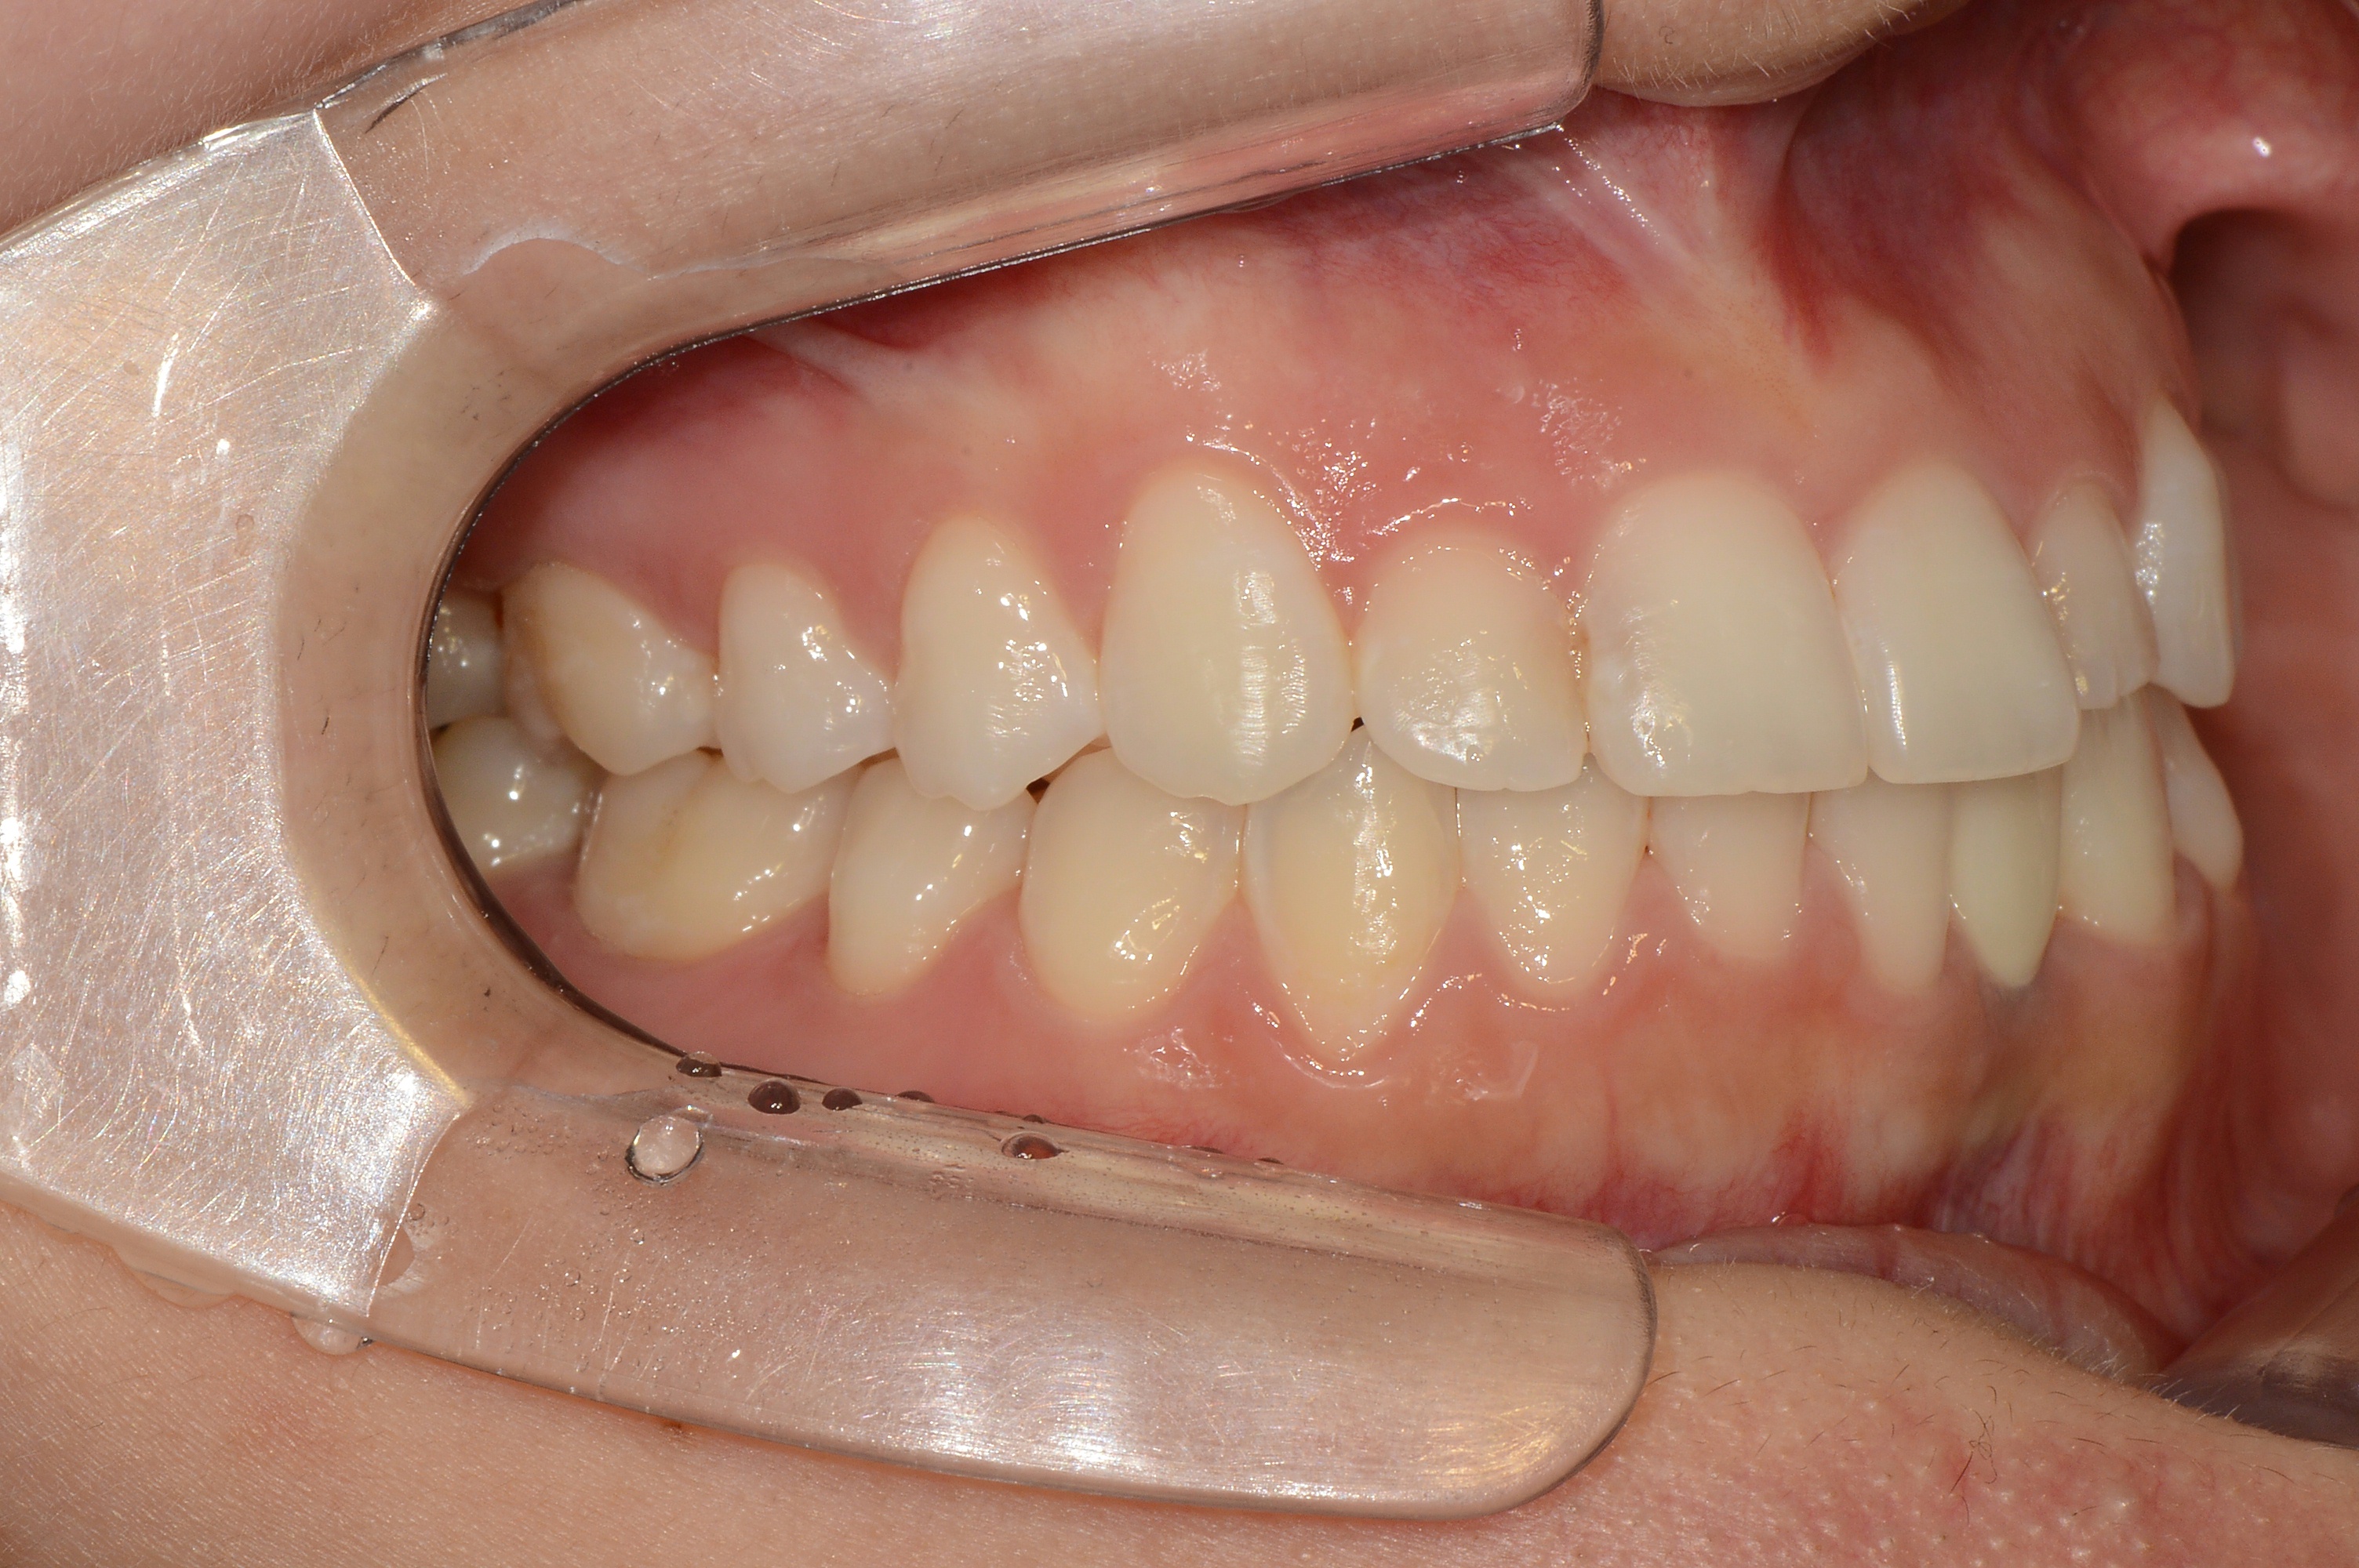

치료 후 사진입니다.